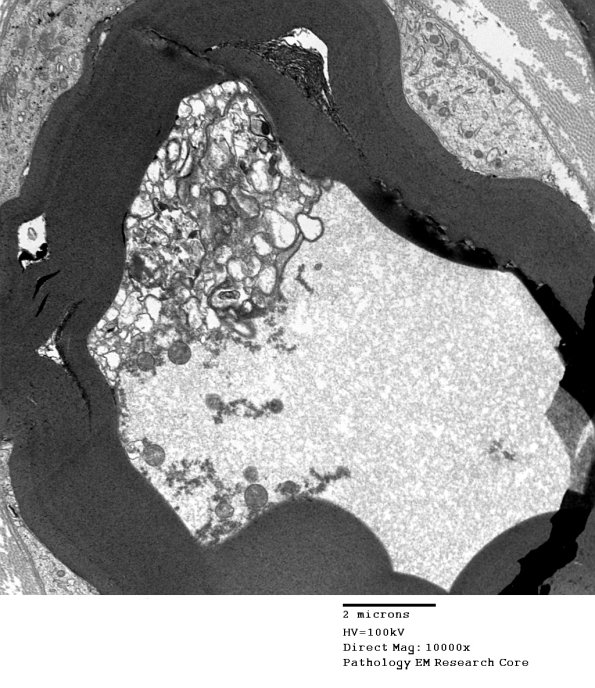

The inner adaxonal Schwannian cytoplasm contains a large number of cytosomes, many degenerating